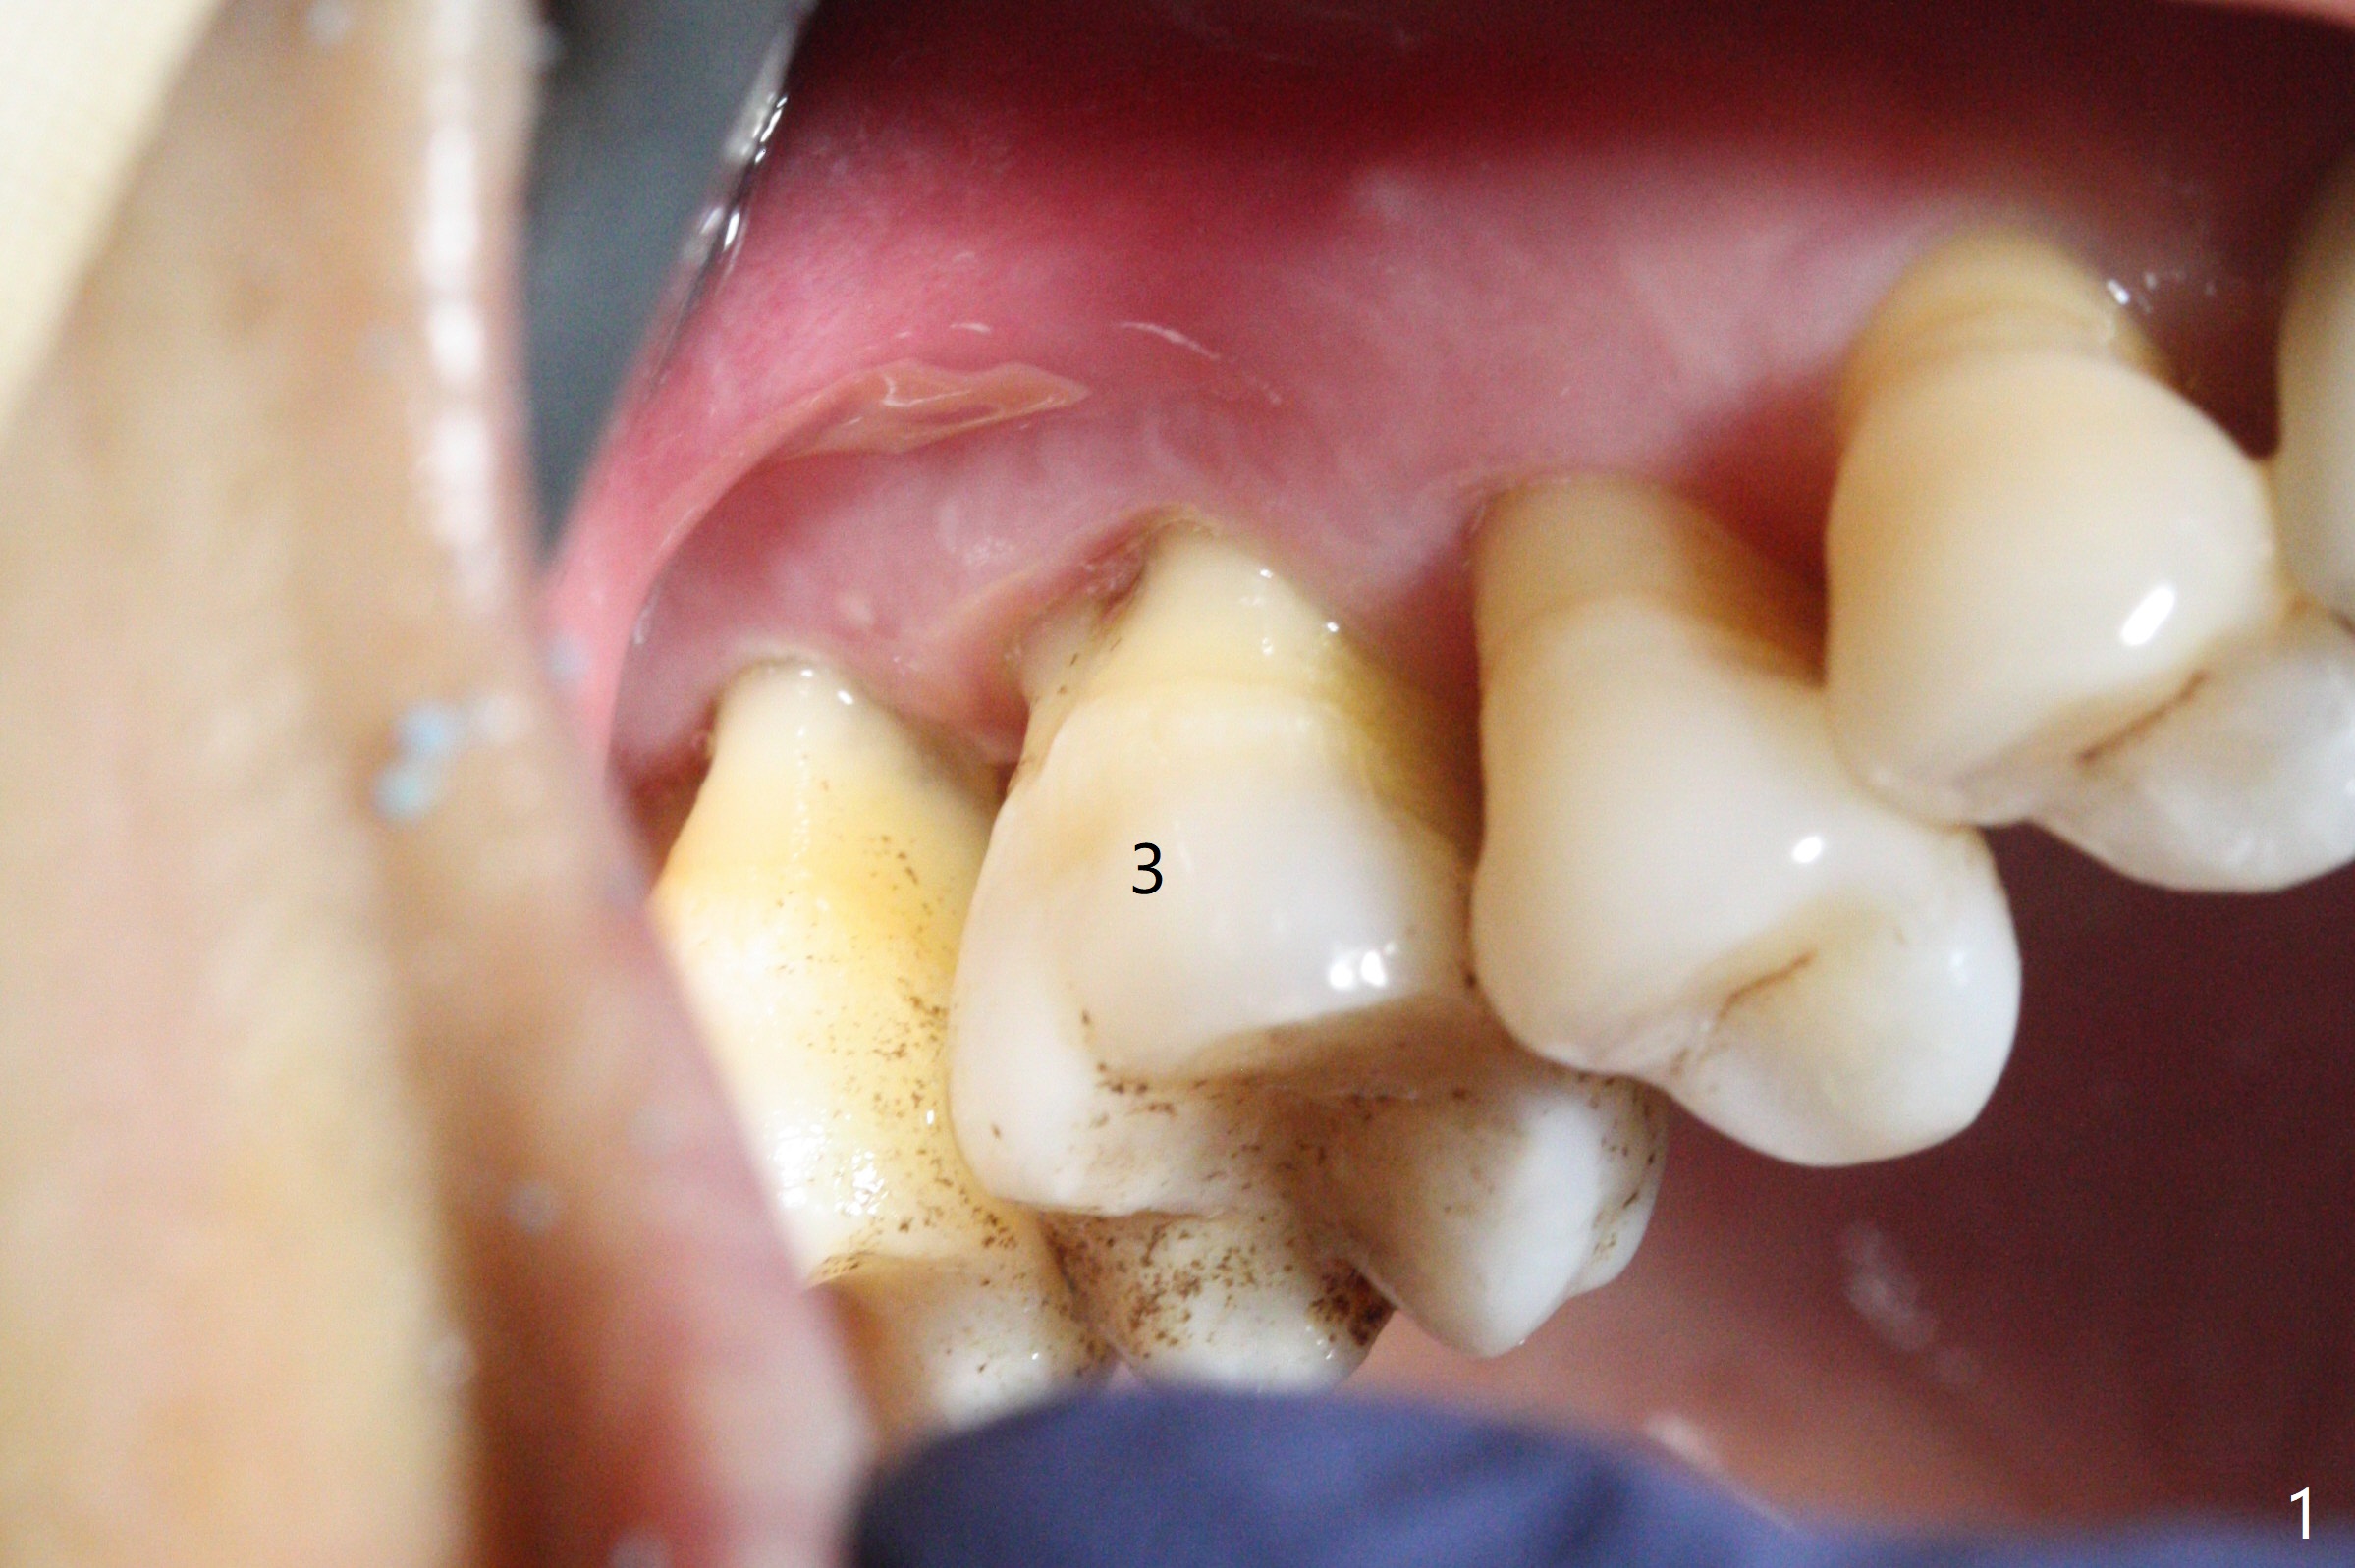

The tooth #3 has gingival recession moderate buccally (Fig.1) and severe palatally (Fig.2 P). The remaining bone height is estimated 4 mm (Fig.3). After extraction and debridement, the 3 sockets are packed with 2% Lidocaine 1:50,000 Epinephrine saturated gauze (Fig.4). When the gauze is removed from the buccal sockets (Fig.5 black area), the buccal portion (B) of the septal gingiva (*) is sectioned from the buccal gingiva (Fig.6 curved white line) and elevated from the underlying septal bone and pushed palatally (arrow). The septal gingiva (including the buccal portion) will be the palatal soft tissue wall of the subsequent osteotomy, providing blood supply to allograft to be placed. In short, the septum (through the buccal socket) will be the osteotomy site.